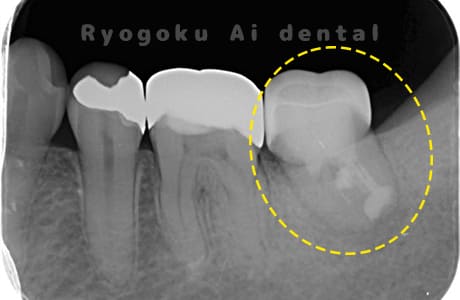

Case02

-

- 原因

- 慢性根尖性歯周炎

- 治療期間

- 1回(消毒・洗浄も含めると3回)

- 治療内容

- 歯根端切除術

- 治療費用

- ¥110,000

他院で抜歯と判断され、インプラント治療を提案された患者様です。被せ物を外さずに、歯の根尖部に外科的にアプローチし、病気の部分を除去しました。

<リスク・副作用>

外科手術のため、術後に出血、痛みや腫れ、違和感を伴います。口腔内の状態によっては適応できないことがあります。歯根端切除で治らなければ抜歯を検討しなくていけない場合もあります。